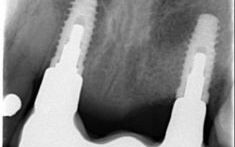

The first step is finding out if you are a good candidate for implant placement. The Doctors need to make sure you have enough bone to hold an implant in place.

We would send you for an evaluation with our periodontist, at that time he would examine you and possibly sends you for a scan to check your bone levels.

About implant dentistry

Most cases it is a single surgical procedure where the periodontist will place the implant in your jawbone and a healing cap above the gum line. After 3 month the periodontist will review the implant for the final stage of treatment. There are some circumstances where the implant will stay under the gum for 3-6 month while it hardens in the bone.

The next step is for the periodontist to uncover the implant from the gum and put a neck on the implant. You will then come back to Kissing Point Dental to have a crown attach to the implant.